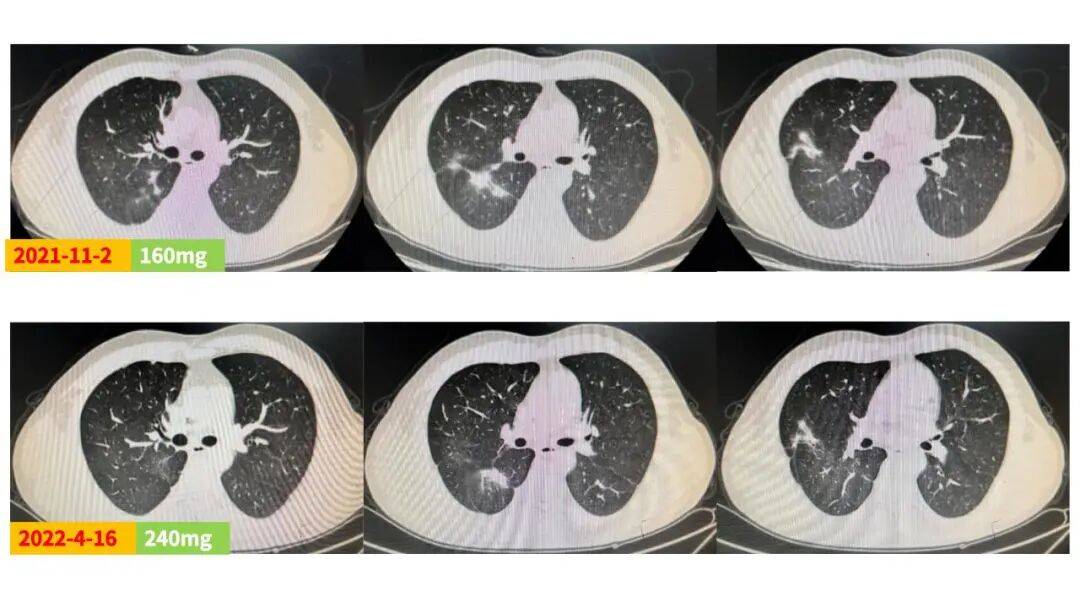

王韵 医生

该例EGFR ex20ins突变晚期NSCLC患者,合并胸膜转移,一线接受标准化疗联合贝伐珠单抗治疗后达SD,但在维持阶段提示疾病进展(PD)。在制定二线治疗方案时,主要考虑以下三大因素:第一,患者不具备条件参加EGFR 20ins相关临床试验;第二,患者不愿再接受化疗;第三,患者无法承担高昂治疗费用。综合考虑,最终选择了性价比高的第三代EGFR-TKI伏美替尼作为二线治疗方案。基于既往试验数据,高剂量伏美替尼疗效更佳,遂为患者进行剂量爬坡治疗。结果显示,伏美替尼80mg治疗两个月后疗效评估即达SD,且随着剂量增加,肺内病灶缓慢缩小,剂量240mg维持治疗期间病灶稳定,持续获益。同时治疗期间安全性良好,仅出现2级皮疹和睫毛增长,未见其他毒副反应。

近年来随着研究的不断深入与探索,三代EGFR-TKI在EGFR ex20ins突变晚期NSCLC前线治疗中展现出了巨大的潜力。FAVOUR研究[1]显示,伏美替尼240mg QD在 EGFR ex20ins突变晚期NSCLC初治和经治患者中的客观缓解率(ORR)分别为78.6%和46.2%,疾病控制率(DCR)分别为100%和92.3%,已有患者持续接受治疗并获得疾病缓解超26个月,且安全性良好。结合本例患者情况,为保证治疗的安全性及提高依从性,起始采用伏美替尼80mg剂量治疗,两个月即迅速达SD,患者快速恢复治疗信心,后续剂量爬坡至160mg和240mg剂量,肿瘤状况均持续稳定,最终采用240mg持续治疗,疾病控制稳定且安全性良好,仅出现2级皮疹和睫毛增长,充分展现了伏美替尼的出色疗效和安全性优势。